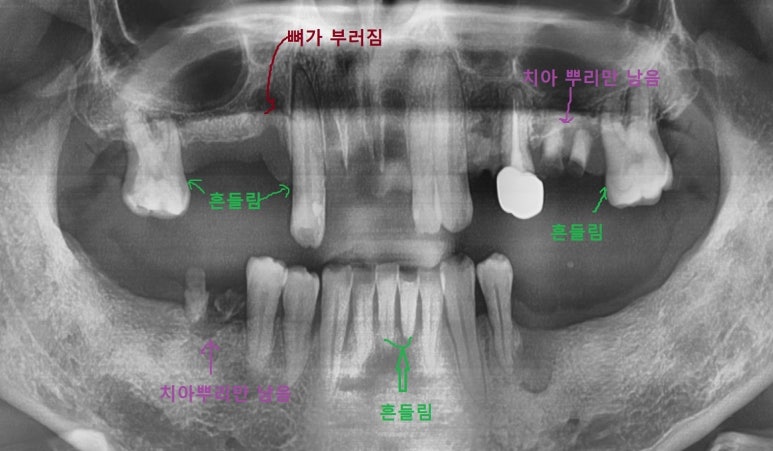

이 40대 환자분은 나름 젊은 분인데 좀 심한 케이스라

파노라마 사진으로 일단 보여드릴게요

외상 케이스라고 할 수 있죠.

사실... 싸우면서 뼈도 부러지고 하셔서

표시된 부위 CT사진을 보면 뼈가 부러진 걸 볼 수 있습니다.

그 부위 치아는 건드리면 흔들흔들 움직이는 상태였습니다.